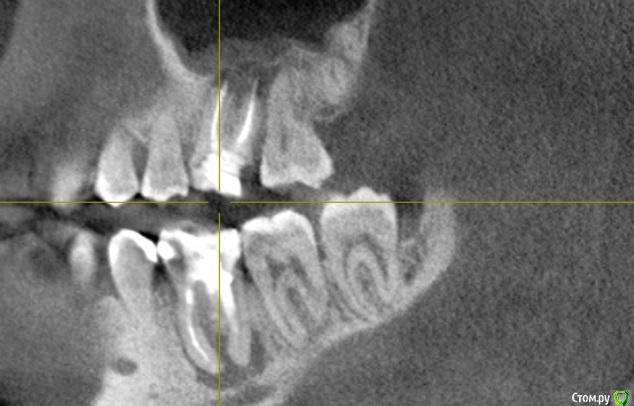

WHITE_ANTONIO Опубликовано 7 декабря, 2015 Автор Поделиться Опубликовано 7 декабря, 2015 Добрый вечер, прикладываю скриншоты КТ Ссылка на комментарий

DmitrySH Опубликовано 7 декабря, 2015 Поделиться Опубликовано 7 декабря, 2015 Прицельный снимки еще будут нужны, в хорошем качестве.26 - ничего особого не видно, просто периодонтит36 - перерасширены каналы, возможно наличие трещины или перфорации.16,46 - тоже требуют лечения Ссылка на комментарий

DmitrySH Опубликовано 7 декабря, 2015 Поделиться Опубликовано 7 декабря, 2015 (изменено) на основании данного снимка судьба зуба 36 под вопросом,а 26 - непонятно, но пока не увидел ничего ужасного. Изменено 7 декабря, 2015 пользователем DmitrySH Ссылка на комментарий

DmitrySH Опубликовано 7 декабря, 2015 Поделиться Опубликовано 7 декабря, 2015 Но я не смотрю на очаги воспаления, меня интересует целостность твердых тканей зуба. Исходя из этого и строится прогноз. На КТ любой материал "фонит" и выглядит больше чем есть. Соответственно есть непонятные моменты. 1 Ссылка на комментарий